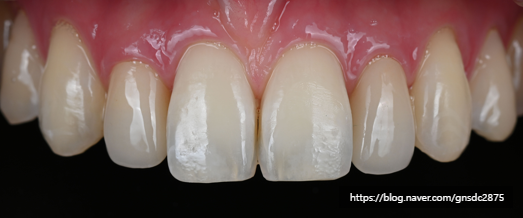

뉴티스 치아성형: 법랑질 다듬기

뉴티스 치아성형은 미세한 치아 깨짐이나

길이가 다른 치아 절단면을 다듬어

가지런하게 만드는 데 목적이 있습니다.

미세한 형태 개선으로

손상없이

치아 가장 겉면에 위치하는

단단한 법랑질을 미세하게 다듬기 때문에

치아 손상이 없고

원하는 형태로 치아를 개선할 수 있습니다.